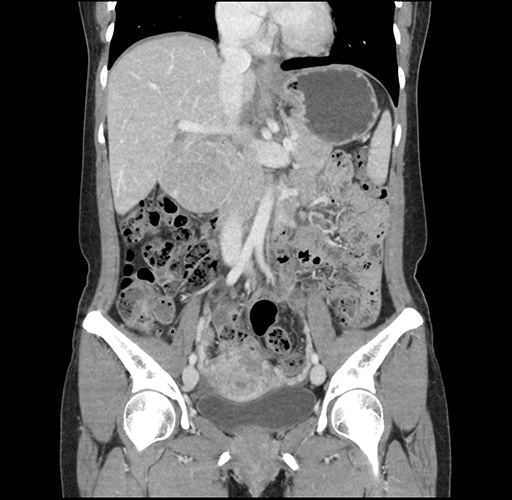

Left lateral sectionectomy [case 12]

Imaging Analysis

Look through the patient's CT scan to identify any areas of concern for the necessary procedure.

Based on your CT findings, which issue(s) would give reason for "planned slowing down moment(s)" in this case?

Considering a standard left lateral sectionectomy procedure, what step(s) of the operation would you do differently in this case ?